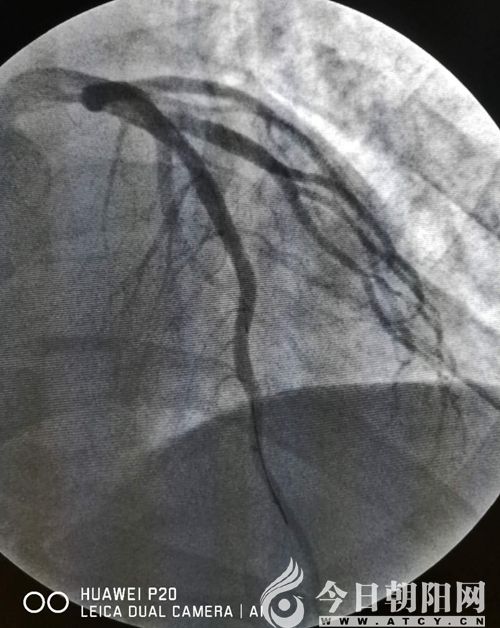

趙某術(shù)前

趙某術(shù)后

緊接著,來不及松上一口氣的胸痛中心團(tuán)隊又開始為患者趙某實施手術(shù)。該患者冠脈前降支近段100%閉塞,單爽為其實施球囊擴(kuò)張術(shù),并植入支架一枚,患者胸痛得以緩解。